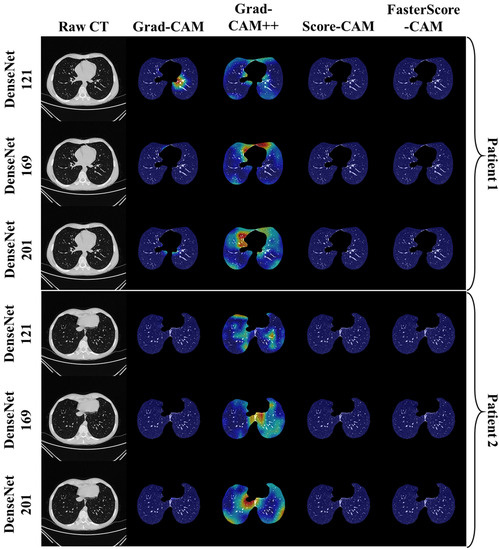

Visual Results Representing Lesion Using the Four CAM Techniques

4.4. A Special Note on Four CAM Models